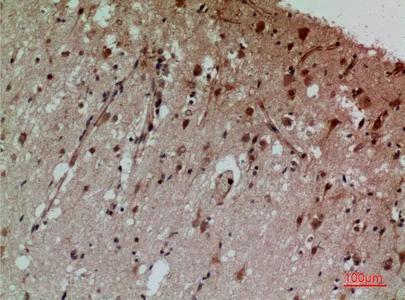

CD13 Rabbit Polyclonal Antibody

Cat: APRab08201

Size1:50μl Price1:$118

Size2:100μl Price2:$220

Size3:500μl Price3:$980

Size2:100μl Price2:$220

Size3:500μl Price3:$980